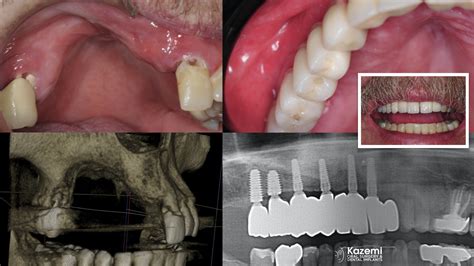

Cone Beam CT (CBCT) Provides a 3D view of the jaw, allowing for precise mapping of bone volume before procedures like implants.

• Bone Grafting: This involves placing synthetic or natural bone material into the area of loss to encourage the body to grow new, healthy bone.

• Guided Tissue Regeneration: A special membrane is used during surgery to prevent fast-growing gum tissue from filling the bone defect, allowing the bone cells the time and space they need to regenerate.

• Periodontal Flap Surgery: The gums are lifted back to allow for a thorough cleaning of the roots and, if necessary, to reshape the damaged bone.

💡 Note: Bone grafting is often performed in conjunction with dental implant placement to ensure the implant has a stable foundation to anchor into.